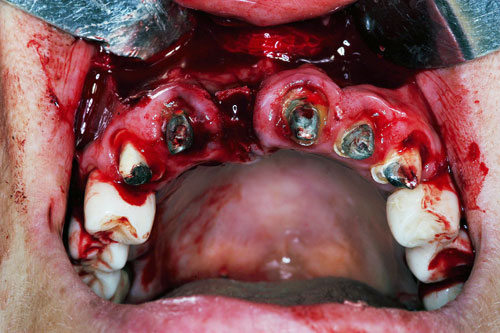

Mientras dichos movimientos ortopédicos se producen (período que supondrá otros seis meses), estudiamos los actos quirúrgicos a realizar en los cuatro implantes que pondremos. De acuerdo al estudio Desatascan realizado observamos tres situaciones diferentes: 1º-El Primer Molar Inferior Izquierdo, lo instalamos mediante Cirugía Minimamente Invasiva , con la aplicación de una Férula Quirúrgica Obtenida de los datos del scanner tratados con un programa de CMI (Cirugía Minimamente Invasiva), previa prueba en un modelo estereolitográfico, ya que la altura ósea era apenas de 9 mm. 2º- El Primer Molar Superior Derecho, se implantará mediante una ligera Elevación Atraumática (Trans alveolar) de Seno una vez logrado el espacio mesio distal necesario. 3º- El Incisivo Central Superior Derecho ausente, cuenta con un sustrato óseo prácticamente inexistente. El espesor de la tabla era de menos de 2 mm. Los caminos posibles a seguir para contar con una Rehabilitación de piezas independientes son dos: Optamos por esta segunda opción por ser menos cruenta y no necesitar de una zona dadora. Técnica esta que pondremos en práctica en dos etapas diferidas: 1º-Incisión horizontal palatinizada, incisiones peri rodetes gingivales e incisiones de descarga. Dilatación que comenzamos con dos incisiones de descarga sobre la cortical vestibular realizadas con disco. y el comienzo de la dilatación propiamente dicha mediante una hoja de bisturí, para luego seguir con un periostótomo . Recién después de alcanzada una cierta separación de la cortical vestibular de la palatina, empezamos con los dilatadores roscados. En este punto podríamos haber utilizado sin riesgos un Implante de 3,8 mm de diámetro, pero a fin de mejorar la estética del pilar emergente decidimos rellenar con material osteoconductor y osteoinductor (BiOss) y cubrir mediante membrana reabsorvible ( Bio Guide). 2º-Implantación seis meses después. Mientras se van cumpliendo los tiempos antes mencionados, y comprobamos reiteradamente la funcionalidad de la oclusión con los provisorios, tomamos impresiones definitivas y construimos primero el maxilar inferior, para definir en primer término la porción inferior de la Guía Anterior., y a nivel posterior Curvas y Microplanos. Para luego realizar los cuadrantes premolar- molar del superior: La espera de la regeneración ósea y sus tiempos pertinentes, más la espera de los tiempos de la implantación, nos obligaron a modificar las etapas del protocolo D.AT.O de manera de mantener la –D- mediante el sector superior de la GA. en provisorios, mientras fuimos resolviendo en forma definitiva los demás sectores. Ya pasados los meses necesarios para recrear un hueso adecuado en el área del Incisivo Superior Derecho, procedemos a resolver la implantación de dicha zona, observando que todo el esfuerzo dedicado al mismo había sido inútil, ya que la formación de hueso se produjo minimamente. Cuatro meses después tomamos impresiones del sector Antero Superior de la Guía Anterior, incluyendo el arrastre de un transfer . Seguimos modelando la encía con un nuevo juego de provisorios. Y se construye entonces el sector superior de la Guía Anterior. Se efectúa un control radiográfico a los 6 meses. Se ha intentado mostrar en esta Rehabilitación, que a pesar de las distintas circunstancias de cada paciente, siempre debemos tener en cuenta la necesidad de ejercer la DESOCLUSIÓN del caso como prioridad número uno, para luego perseguir la ALINEACIÓN TRIDIMENSIONAL de las arcadas y obtener así una OCLUSIÓN equilibrada. D.AT.O. ES EL PROTOCOLO QUE DEBEMOS SEGUIR EN TODA REHABILITACIÓN. BIBLIOGRAFÍA 1)William Mc Horris,B.S.,D.D.S. Oclusión. Con especial énfasis sobre :El rol funcional y parafuncional de los dientes anteriores. 2)Von Spee , Craff(Anatomista alemán, describió la curva de compensación de la articulación de molares y premolares).CURVA DE SPEE 1.89 3)Stuart,D.”Some aspects of the inervation teeth.”Procedings of Royal Society of Medicine.20:1675,19274)Muhleman,H. y Savdir,S”Tooth movility-its causes and significance”Journal of Periodontology ,36:153,Marzo ,Abril,1965. 4)Muhleman,H. Y Savdir,S”Toothmovility its causes and significance” Journal of Periodontology,36:153,marzo,abril,1965. 5-Oclusión y Diagnóstico en Rehabilitación Oral. 6-Anatomia Odontológica. 7-A contribution to the study of the movementes of the mandible. 8-Celenza F.W, Nadeskin J.F.,Oclusión.Situación actual. 9-D´Amico 10-Dawson P.E. 11-Huffman –Regenos. 12-Hobo S.-Takayama H.A. 13-Lucia V.O 14-Mc Horris. 15-Mc Horris. 16-Stuart C. 17-Vartan Veshnilian 18-Alvarez Cantoni H. AUTOR:Ratificación del Protocolo en Rehabilitación Bucal a pesar de las incidencias propias de cada caso clínico. A propósito de un caso.

Se utilizarán dos Implantes roscados de 8 mm de longitud por 3,8 mm de ancho.

Verificamos también el escaso ancho crestal, lo que nos obliga a utilizar dilatadores roscados y un osteótomo para elevar inicialmente la membrana de Schneider.

No obstante pudimos implantar satisfactoriamente mediante un implante de 4.2 mm. de ancho y 14 mm. de largo, con una nueva R.O.G.

El implante se encontraba perfectamente según comprobaciones radiográficas y clínicas al sondeo.